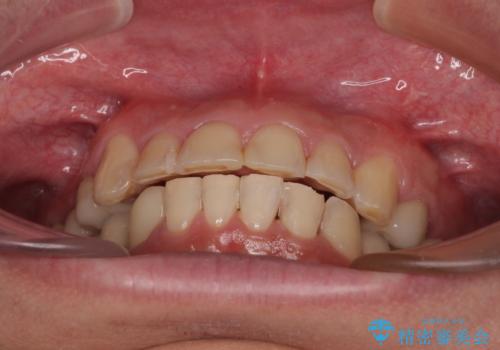

銀歯を白くしたい 一緒に矯正治療も行ない美しい口腔内に

矯正治療にやや時間がかかりましたが、歯列はきれいに整い、気になっていたむし歯や銀歯は自然な色合いに仕上がりました。